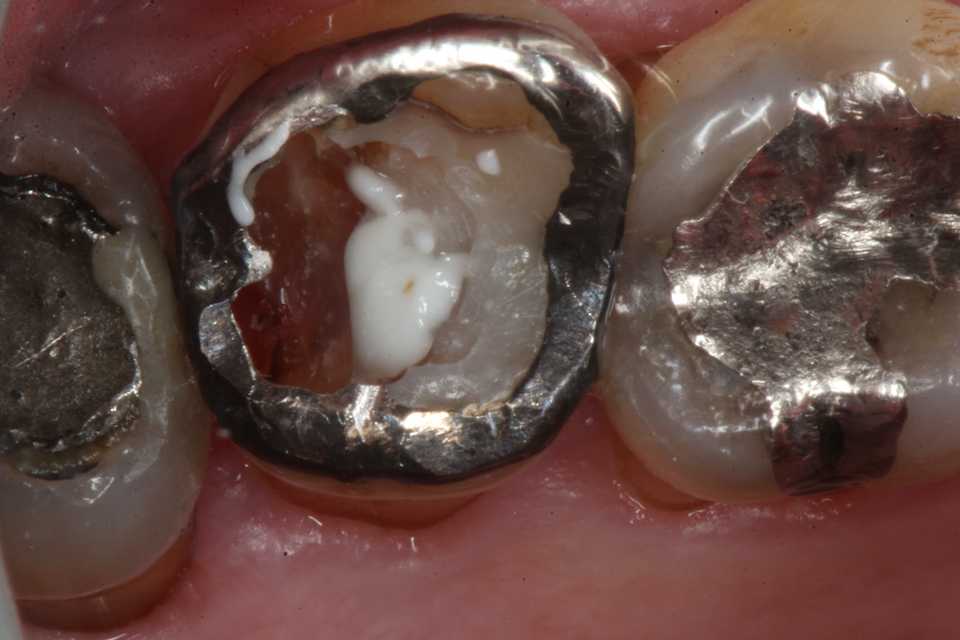

70代男性、左上7、外傷性咬合、自発痛-

応力腐食割れ ​」に似た腐食(虫歯)が発生する。

補強冠を入れて崩壊を防いでいたが、とうとう遠心隣接面が崩壊した。切削バーもスプーンエキスカベータも届きにくいし、歯肉側のエナメル質も失われていて、象牙質も軟化象牙質に近くなっている。

直視下ではこんな感じで、患部が見えないのでミラーテクニックが必要になるが、器具も届きにくいので術者も絶望的な気分になる。